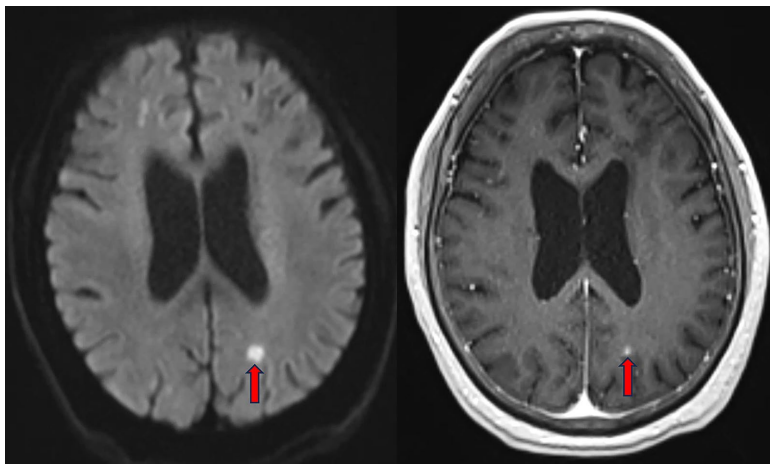

腹部增强CT显示右肝叶脓肿伴右肝静脉分支脓栓形成,红色圈注区域清晰显示直径>5cm的液化坏死灶。胸部CT呈现双肺多发性斑片状实变影,符合血行播散性肺炎特征。值得注意的是,在初始碳青霉烯类抗生素治疗10天后,患者出现神经系统症状,脑MRI在双侧额顶枕叶及小脑半球检出多发强化病灶,扩散加权成像(DWI)序列左枕叶高信号区提示化脓性脑炎。

研究揭示了高毒力株的三大致病特征:rmpA基因介导的荚膜多糖超量产生形成"免疫逃逸盾牌";铁载体(siderophores)在糖尿病低铁环境中疯狂增殖;colibactin毒素加速组织坏死。腰椎MRI的T2加权像清晰显示L4-L5椎体及椎间盘异常高信号,红色箭头标注的腰背部软组织感染灶印证了细菌的"组织嗜性"。